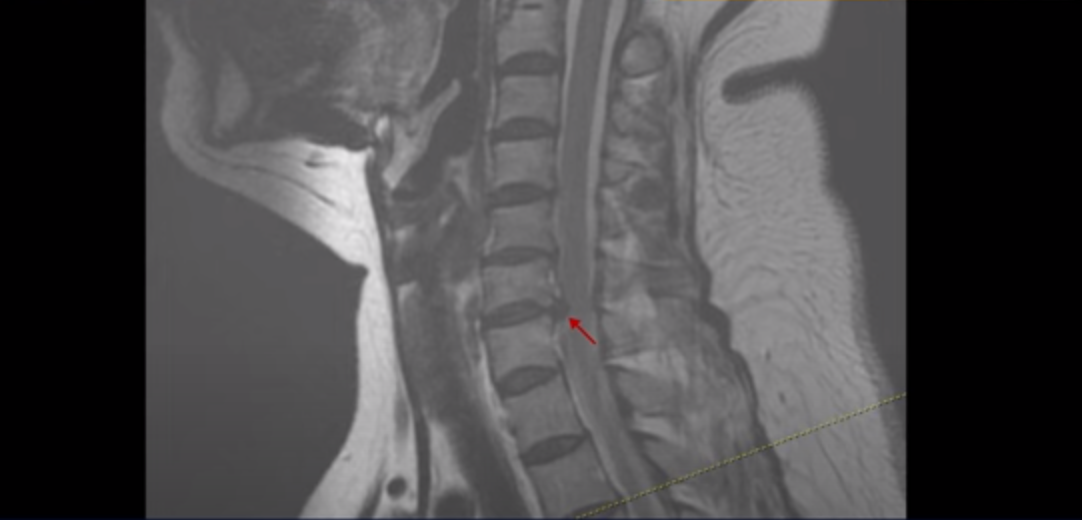

우선 이분 MRI를 보면 목디스크 6번 7번에 오른쪽으로 디스크가 터져서 밀려 나와 있습니다. 이 문제가 오른쪽 팔 통증과 견갑골 통증을 일으키는 걸로 보입니다.

4번 5번과 5번 6번에서도 신경길이 좁아져있지만 왼쪽 방향이라 오른쪽 방사통은 이 6번 7번 디스크 때문으로 보입니다.